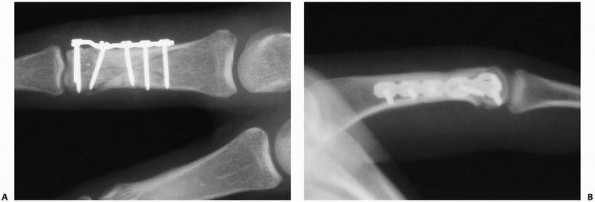

effective for spiral fractures. When comminution or axial instability

appropriately treated with plate and screw fixation (Fig. 28-30).

FIGURE 28-30 More complex shaft fractures (A) can be stabilized by (B,C) multiple lag screws or (D) a lateral plate and screws.